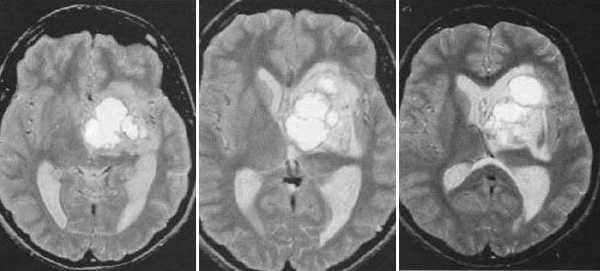

Злокачественная смешанная герминативноклеточная опухоль. В боковых желудочках и пинеальной области определяются множественные опухолевые узлы с выраженным перитуморальным отеком. Внутрижелудочковые образования с признаками кровоизлияний. При в/в контрастировании определяется выраженное контрастирование узлов. Дополнительно визуализируется метастазирование по эпендиме боковых и IV желудочков мозга.